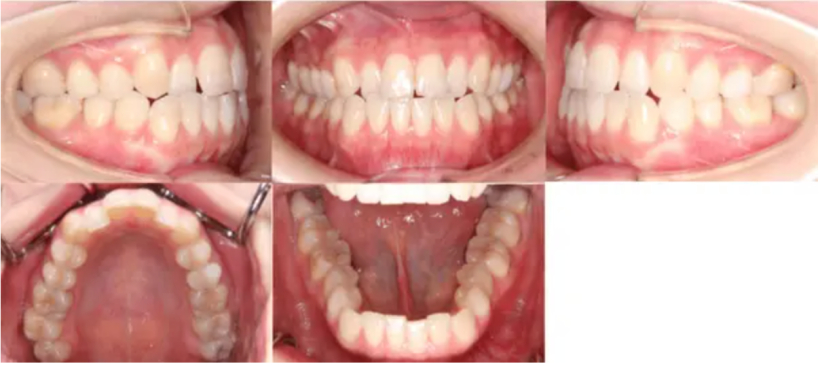

【治療後】

治療例①②のように部分矯正によって改善された事例もありますが、部分矯正から全顎矯正に変更したことで歯並びが揃った症例もあります。